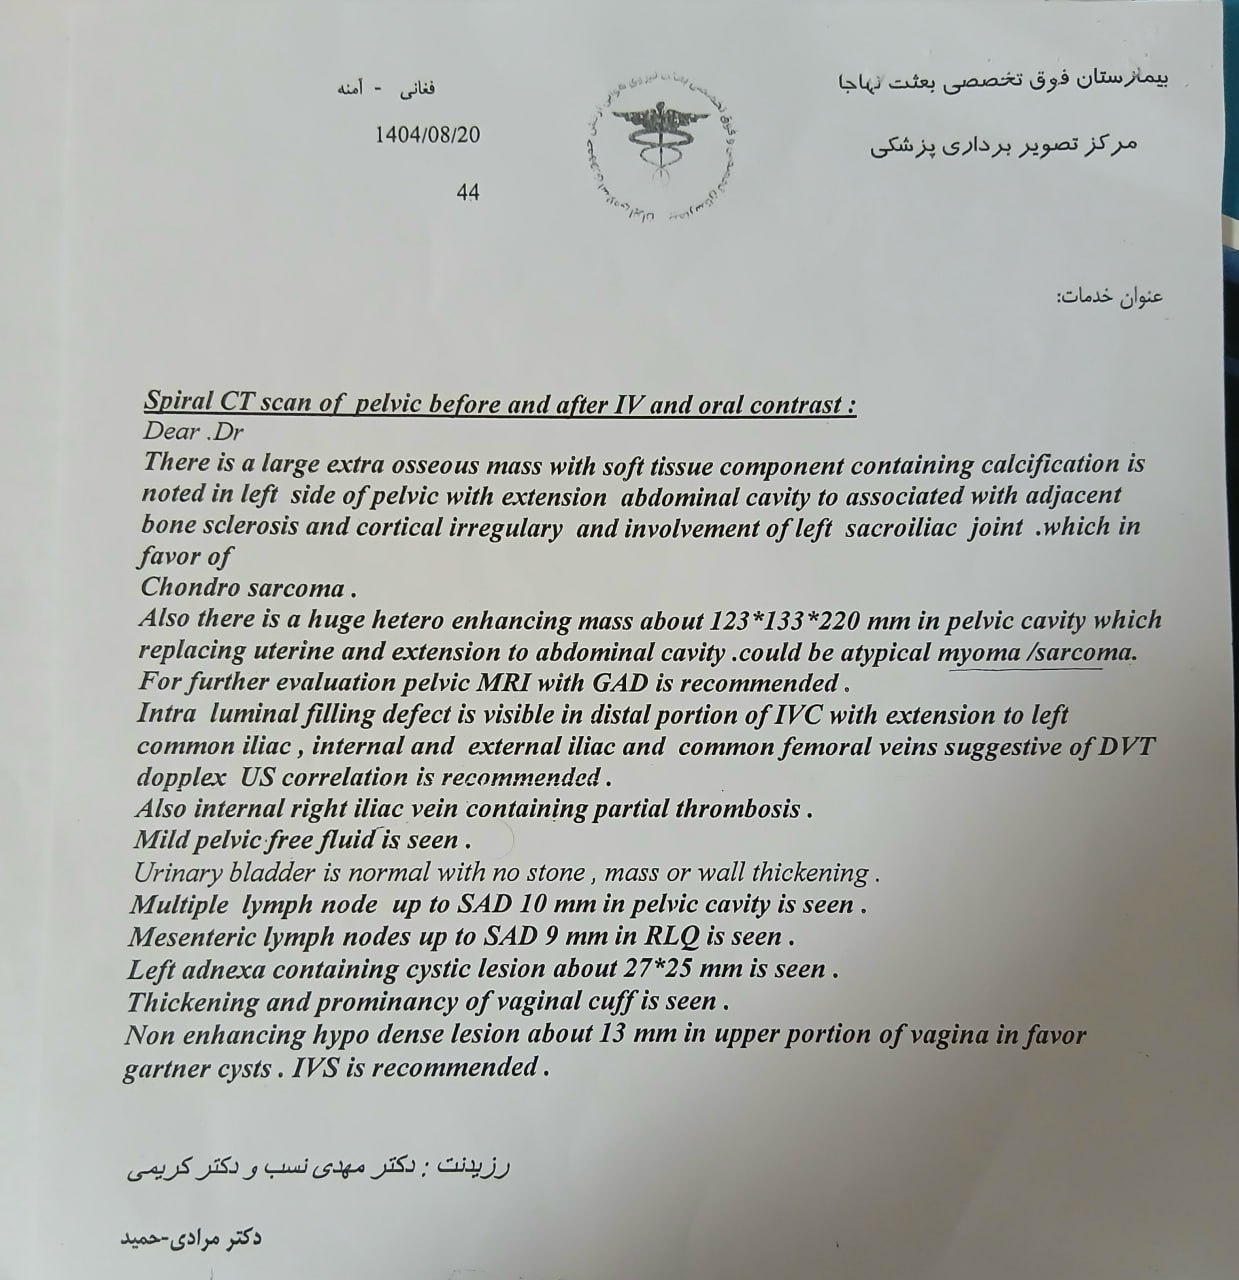

در بررسیهای تصویربرداری (MRI)،در تاریخ 24.7 ، تودهای با تشخیص کندروسارکوما همراه با DVT گزارش شده است. بیمار سابقه درد لگن داشته که شدت آن در حال حاضر نسبت به گذشته کاهش یافته است. به گفته بیمار، حجم توده در ابتدا در حدود اندازه یک تخممرغ بوده که در حال حاضر کاهش یافته است. همچنین تورم اندام تحتانی در حال حاضر نسبت به قبل کمتر شده است.

بیمار، در تاریخ 18.9 ، به دلیل تورم اندام تحتانی چپ از سرح ران و درد شدید سراسر اندام تحتانی چپ به همراه اختلاف سایز اندام ها در تهران بستری شده است. در بررسیها جهت بیمار تشخیص ترومبوز ورید عمقی (DVT) اندام تحتانی چپ مطرح شده است و تحت درمان DVT قرار گرفته است.

مراجعه کرده است. پس از بررسی های انجام شده در MRI انجام شده توده با درگیری مفصل ساکروایلیاک چپ و DVT؛ ابتدا تحت درمان DVT قرار گرفته است و سپس جهت پیگیری تومور رویت شده تحت بیوپسی قرار گرفته است و با تشخیص کندروسارکوما به این مرکز مراجعه کرده است و تحت کموتراپی و رادیوتراپی قرار گرفته و سایز تومور کاهش یافته است.

(تصویر مربوط به این مراجعه نیست) Other: